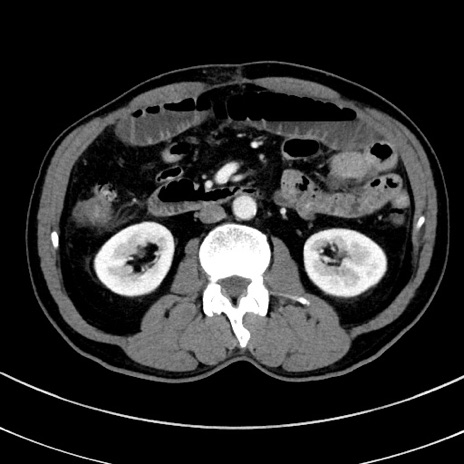

症例8(横断像)

【症例】 60歳代男性

【主訴】 黒色吐物

【現病歴】 4日前から嘔気自覚、2日前の朝食後にも嘔気あり、自分で手で嘔吐反射起こし嘔吐したところ血が混ざっていたため受診。

【既往歴】 5年前汎発性腹膜炎を伴う急性虫垂炎で手術、高血圧、前立腺肥大症、高脂血症

【身体所見】 腹部正中に手術癩痕あり 腹部平坦・軟圧痛なし膨満感あり

【データ】WBC 8400、CRP 4.54